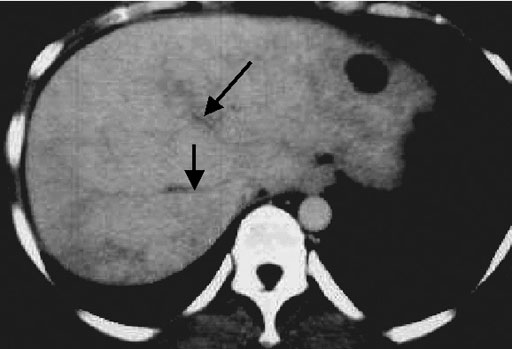

肝静脈は狭小化し、肝実質相であるにもかかわらず、肝静脈は造影されていない(黒矢印)